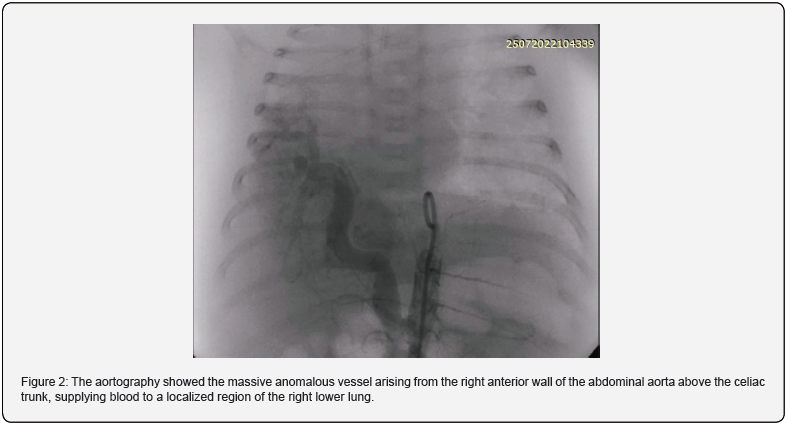

On the 24th day of life, a body weight of 2.8 kg, cardiac catheterization, and angiography via femoral vein and artery with 4-French were performed under general endotracheal an aesthesia. An initial heparin bolus of 100 units/kg was administered. The mean pulmonary artery pressure was 51 mmHg, and the pulmonary to systemic blood flow (Qp/Qs) ratio was 2:1. The right pulmonary artery branch was significantly narrower than the left. Aortography showed the massive anomalous artery arising from the right anterior wall of the abdominal aorta above the celiac trunk, supplying blood to a localized region of the right lower lung (Figure 2). Its narrowest diameter was 4.3 mm; its largest transverse diameter was 6.8 mm, and its length was 19 mm. We selected a device 30% (7 mm) larger than the narrowest artery diameter [Amplatzer Vascular Plug 4]. The device was placed in the second curve via a 4F multipurpose catheter. Control angiography revealed slower flow and low contrast intensity through the deviated blood vessel and the absence of distal translocation of the device. After the procedure, according to the Institutional protocol, a continuous infusion of heparin was prescribed for 24 hours.